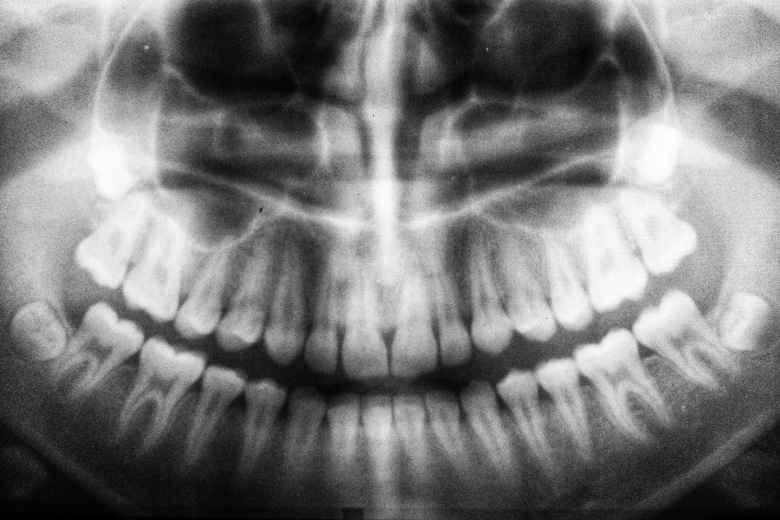

Новозеландский спортсмен австралийского клуба «Канберра Рейдерс» Сиа Солиола получил серьёзную травму в матче Национальной регбийной лиги против «Ньюкасл Дрэгонз».

Во время столкновения с соперником Солиола получил перелом лицевой кости. Спортсмен поделился рентгеном своей челюсти и с юмором отреагировал на ситуацию.

По крайней мере зубы в порядке, — написал он на своей странице в Instagram.